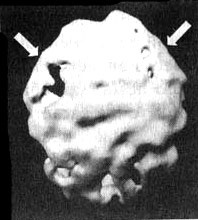

Заболевание Альцгеймера, разрушительная прогрессирующая форма старческого слабоумия, является одной из главных проблем с памятью у пожилых людей. К сожалению, у многих это заболевание крадет годы заслуженного отдыха, а их близких доводит до физического, эмоционального и финансового истощения. Действенным диагностическим методом в таких случаях оказывается SPECT. Прежде чем медикам стали доступны методы функциональной диагностики, единственным достоверным способом поставить этот диагноз было вскрытие. Сканирование SPECT показывает типичное для болезни Альцгеймера снижение перфузии в обеих височных долях и снижение активности в теменных долях. Иногда такая картина возникает за три-шесть лет до появления симптомов. Некоторые новые препараты для лечения этого заболевания, похоже, могут приостанавливать его развитие. В ходе сканирования мы наблюдали, что благодаря их действию улучшается перфузия в тех частях мозга, которые отвечают за память и мышление, в том числе и в височных долях. На иллюстрациях представлен мозг больного синдромом Альцгеймера, который стал забывчивым, часто не мог найти дорогу, когда выходил из дома, стал забывать элементарные вещи, например разучился самостоятельно одеваться и стал проявлять все больше агрессии по отношению к собственной жене. Мозг Хэрриет. Последствия энцефалита ![]() Трехмерное изображение нижней поверхности. Обратите внимание на выражений сниженную активность в обеих височных долях (см. стрелки). Болезнь Альцгеймера ![]() Трехмерное изображение поверхности, вид сверху. Обратите внимание на выраженно сниженную активность в теменных долях (см. стрелки). ![]() Трехмерное изображение нижней поверхности. Обратите внимание на выраженно сниженную активность в височных долях (см. стрелки). Говорят, что «спазмами височных долей» страдал Федор Иванович Достоевский. Он считал свою болезнь «святым переживанием». Один из его биографов, Рене Фюлеп-Миллер, цитирует высказывание Достоевского, что эпилепсия «вызывает во мне чувства, о которых я доселе не подозревал, сообщая мне ощущения блаженства, изобилия и вечности». В своем романе «Идиот» Достоевский пишет: «Он задумался между прочим о том, что в эпилептическом состоянии его была одна степень почти пред самым припадком (если только припадок приходил наяву), когда вдруг, среди грусти, душевного мрака, давления, мгновениями как бы воспламенялся его мозг, и с необыкновенным порывом напрягались разом все жизненные силы его. Ощущение жизни, самосознания почти удесятерялось в эти мгновения, продолжавшиеся как молния. Ум, сердце озарялись необыкновенным светом; все волнения, все сомнения его, все беспокойства как бы умиротворялись разом, разрешались в какое-то высшее спокойствие, полное ясной, гармоничной радости и надежды, полное разума и окончательной причины. Но эти моменты, эти проблески были еще только предчувствием той окончательной секунды (никогда не более секунды), с которой начинался настоящий припадок. Эта секунда была, конечно, невыносима. Раздумывая об этом мгновении впоследствии, уже в здоровом состоянии, он часто говорил сам себе, что ведь все эти молнии и проблески высшего самоощущения и самосознания, а стало быть и „высшего бытия“, не что иное как болезнь, как нарушение нормального состояния, а если так, то это вовсе не высшее бытие, а, напротив, должно быть причислено к самому низшему. И однако же, он все-таки дошел наконец до чрезвычайно парадоксального вывода: „что же в том, что это болезнь?“, решил он наконец, „какое до того дело, что это напряжение ненормальное, если самый результат, если минута ощущения, припоминаемая и рассматриваемая уже в здоровом состоянии, оказывается в высшей степени гармонией, красотой, дает неслыханное и негаданное дотоле чувство полноты, меры, примирения и встревоженного молитвенного слития с самым высшим синтезом жизни?“». Брайс Льюис Кэрролл, по некоторым свидетельствам, тоже страдал «явлениями от височных долей», которые хорошо отражены в зрительных образах Алисы в его книге «Алиса в стране чудес». Семилетний Брайс, которому мать стала читать «Алису», очень разволновался. Он сказал, что чувствует себя как Алиса. «Со мной происходят странные вещи, — рассказал он матери. — Я вижу всякие вещи». Среди бела дня он наблюдал, как предметы меняют свою форму, часто уменьшаясь в размерах. Ночью он видел зеленоватых призраков. У Брайса обнаружилось много симптомов тревожности. Его мать, перепугавшись, что Брайс «сходит с ума» (а его двоюродному брату поставили диагноз «шизофреноподобное состояние»), мать привела его ко мне на прием. Услышав о его симптомах, я заподозрил, что одна или обе височные доли у него гиперактивны. Сканирование SPECT выявило нарушения в правой височной доле и повышенную активность базальных ганглиев. Я назначил Dapakote (противосудорожный препарат, эффективный при лечении поражений височных долей), а также сеансы психотерапии для снижения тревожности. В течение двух недель странные состояния Брайса прекратились, а в течение полугода снизилась и тревожность. Мозг Брайса. Эпилепсия височных долей ![]() Трехмерное изображение нижней поверхности. Обратите внимание на область повышенной активности в глубоких отделах правой височной доли (стрелка снизу вверх) и базальных ганглиях (стрелки вниз). Эллен и Джек У Эллен и Джека похожие истории болезни. Оба были слегка замкнутыми. У обоих случались приступы головокружения и беспричинной паники. У обоих религиозный опыт занимал довольно значительное место в жизни. У Эллен (32 года) глубокие религиозные переживания практически парализовали ее жизнь. Она не могла работать и находилась в социальной изоляции. Джека очень заинтересовали ее «периоды глубокого духовного просветления», но он никак не мог понять, что это означает. Ко мне на прием Эллен привели ее родители, которых беспокоила ее социальная изолированность. Джек хотел обследоваться по поводу приступов паники. В обоих случаях сканирование выявило выраженную гиперактивность глубинных областей в височных долях. Значительная часть их симптомов ушла после того, как они начали принимать Depakote. При этом, продолжая прием этого препарата, оба остаются глубоко религиозными людьми. Правда, они больше не остаются погруженными в свои мысли значительную часть времени, как это было раньше. Джим Как в случае Эллен и Джека, Джима беспокоили приступы головокружения и панического страха. У него тоже бывали периоды «религиозных мыслей», во время которых он ощущал «присутствие дьявола», становился неуверенным и напуганным. Его страх перед дьяволом преследовал его, делал замкнутым. В семье считали, что он страдает паранойей. В результатах сканирования мозга Джима выявилось интересное отличие от результатов Эллен и Джека. У Джима нарушения обнаружились в левой, а не в правой височной доле. На основании своего опыта я полагаю, что нарушения именно в левой височной доле проявляются особенно негативными или мрачными мыслями. После того как Джим стал принимать Depakote, «присутствие дьявола» завершилось. |